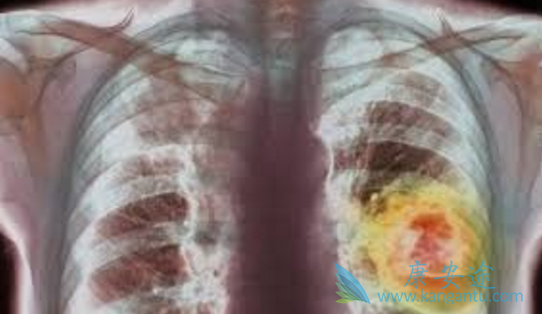

印度易瑞沙是我国肺癌患者最受青睐的一线用药,不仅价格便宜,治疗效果也与原研药一样。那对于特殊人群服用易瑞沙,治疗效果是否有差异呢?一项包括41例实体肿瘤伴有肝转移,而肝功能正常、中度或重度损害的患者的临床研究中对吉非替尼进行评价。研究显示,口服吉非替尼每日剂量250mg后,达到稳态时间、总的血浆清除率和稳态药物暴露水平在肝功能正常组和中度损害组结果相似。